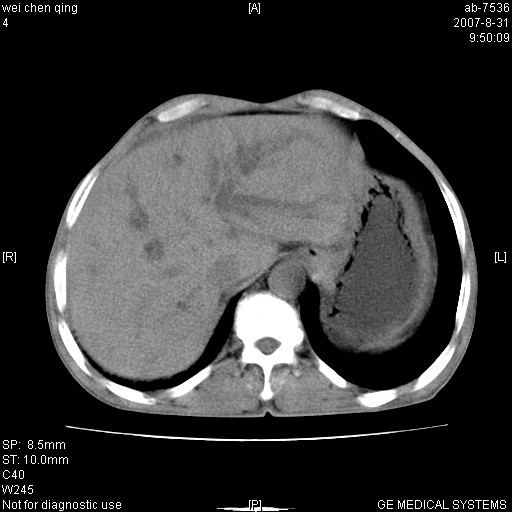

以下是引用zyyzzy在2007-8-31 14:34:00的发言:[br]该病人肝内胆管扩张,胆囊及胆总管未见明显扩张。在倒数第9层图像上可看到左右肝管结合部(肝总管)有软组织影,此处应薄层扫描。考虑肝总管占位(ca)、腹水。[br]